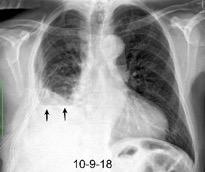

Síndrome de afectación postcardiaca (postcardiac injury)

Post infarto 1-7 % (Dressler)

Trauma cerrado Implantación marcapasos

Cirugía cardiaca. 17-31% (Post.pericardiotomía)

3707 pacientes 29 Derrames (0,78%) > de 25% del hemitórax

Todas menos 2 Izdos.

Angioplastia

By-pass coronario 21-10-03